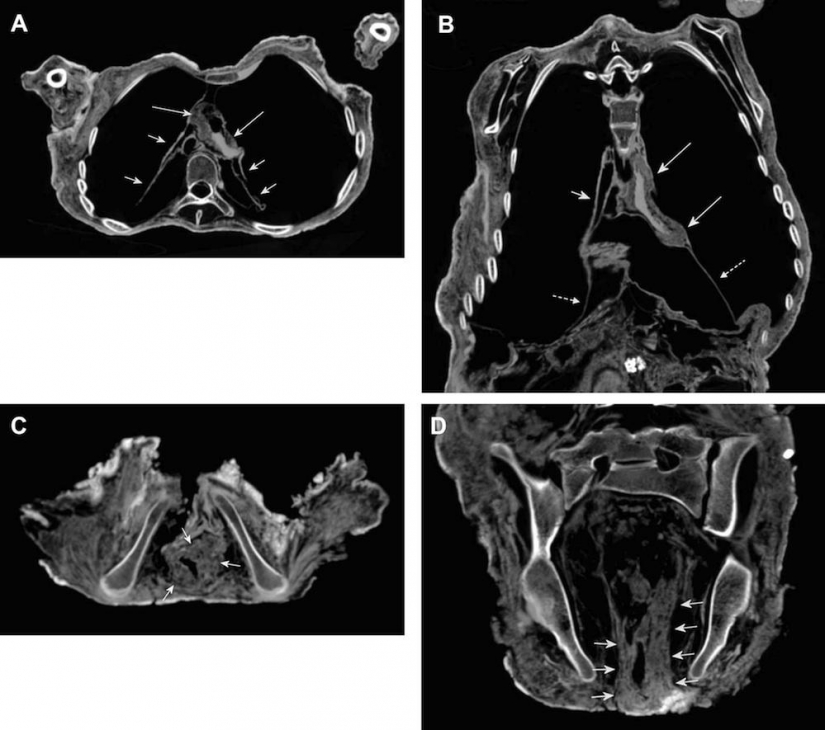

16. Las imágenes también mostraron signos de la compactado de la pared del corazón y una inflamación del intestino. Probablemente, esto fue causado por la enfermedad de Chagas.

17. Los rayos X del cuerpo del Inca momias.